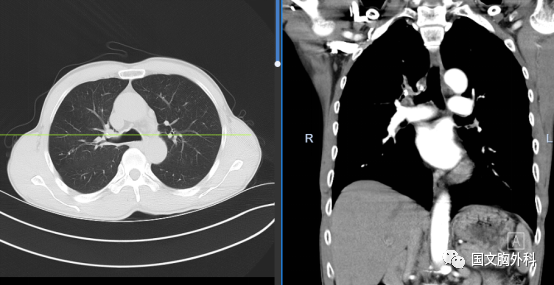

周大爺,發(fā)現(xiàn)肺占位1個(gè)月。CT下觀察右肺上葉腫物延續(xù)至肺門(mén),穿刺病理提示:肺鱗癌。有手術(shù)機(jī)會(huì),家屬同意手術(shù)治療。

術(shù)中患者右肺門(mén)分離困難,決定行右肺上葉袖型切除,在長(zhǎng)達(dá)8小時(shí)的奮斗后,周大爺手術(shù)順利結(jié)束。